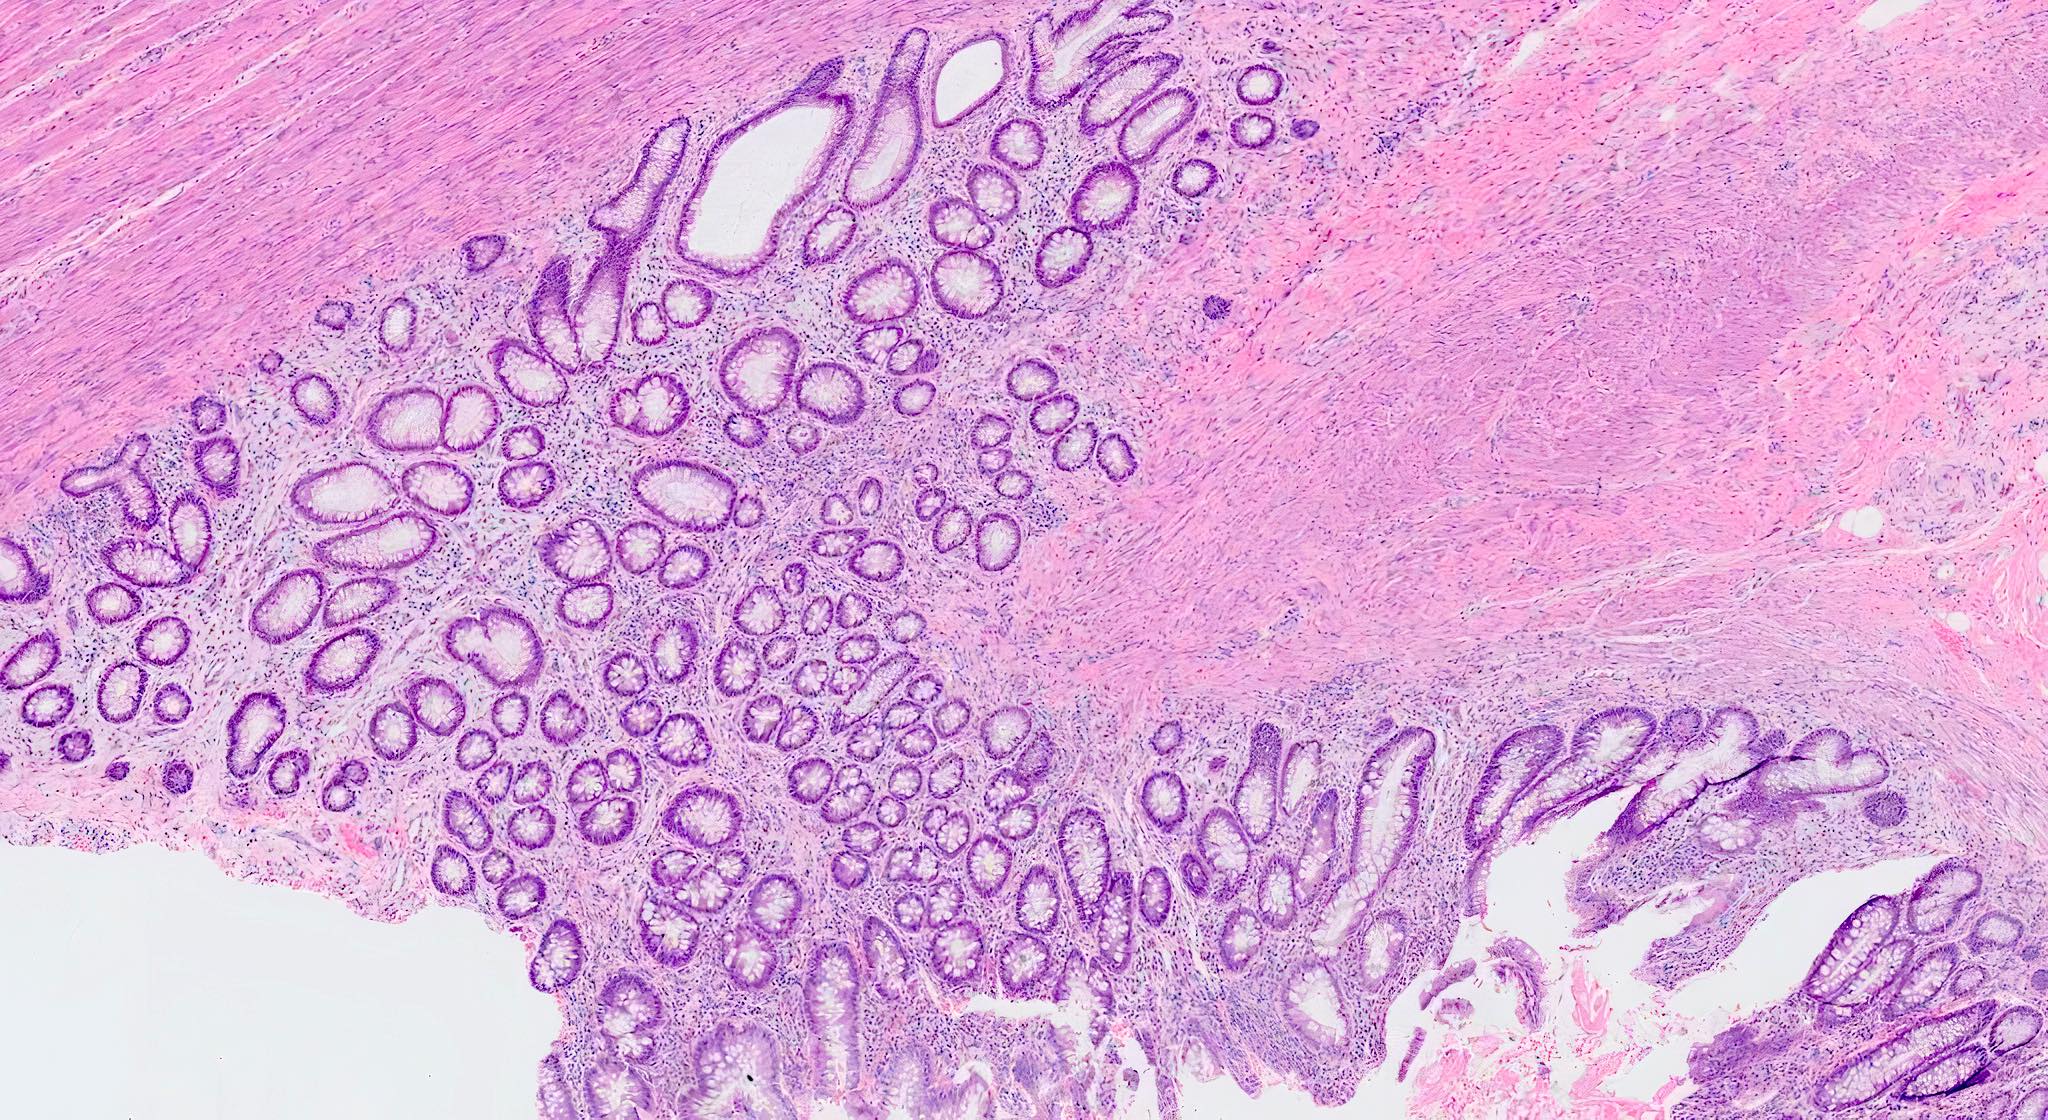

Microscopic (histologic) description

- Mucosa may be normal to markedly abnormal

- Expansion of lamina propria by lymphoplasmacytic infiltrate (more prominent in basal half)

- Lymphoglandular complexes, mucin depletion, focal Paneth cell metaplasia (in chronic cases) may be seen (J Clin Gastroenterol 2004;38:S11)

- Muscularis mucosa extends towards surface between elongated crypts

- Shortening of the affected bowel and hypertrophy of circular muscle layer (myochosis) leads to exaggerated mucosal folds (Am J Surg Pathol 1991;15:871)

- Some cases can show lamina propria fibrosis, crypt elongation on the tips of prominent mucosal folds, like mucosal prolapse syndrome in rectum and anus (J Clin Gastroenterol 2008;42:1137)

Microscopic (histologic) images

Contributed by Bindu Challa, M.D. and Martha M. Yearsley, M.D.